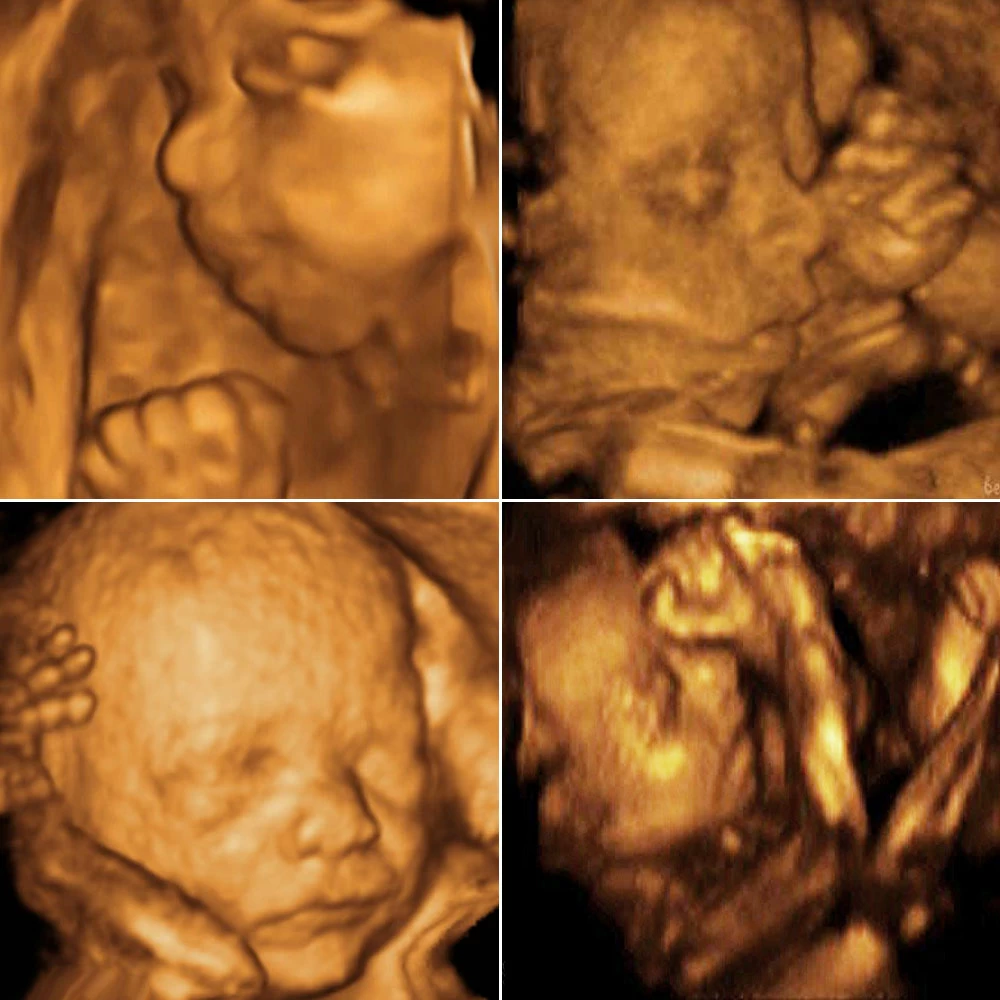

Неделя № 12

Копчиково-теменной размер плода составляет 50-60 мм.

Отчетливо идет развитие половых органов по женскому или мужскому типу.

Кишечник вытягивается в длину и укладывается петлями, как у взрослого человека. Начинается его периодические сокращения – перистальтика. Плод начинает совершать глотательные движения, заглатывая околоплодные воды.

Головной мозг имеет маленькие размеры, но точно повторяет все структуры мозга взрослого человека, плод может сжимать и разжимать пальцы в кулак, захватывает большой палец и активно его сосет.

В крови плода уже присутствуют не только эритроциты, но и начинается выработка белых кровяных клеток – лейкоцитов.

В это время у ребенка начинают регистрироваться единичные дыхательные движения. До рождения плод не может дышать, его легкие не функционируют, однако он совершает ритмичные движения грудной клетки, имитируя дыхание.

К концу недели у плода появляются брови и ресницы, хорошо заметна шея.